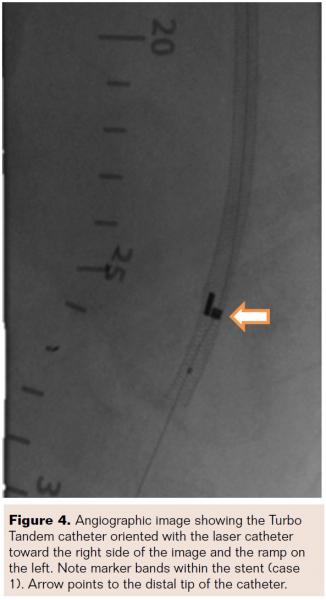

After the TE was removed, the 7 Fr TT was then positioned at the proximal portion of the lesion. Settings were adjusted to 40 fluence and 30 Hz, but were raised after 4 initial passes to 80 fluence and 80 Hz because higher laser settings allow more efficient ablation and tissue removal. The stent provides added structural support to the vessel so the higher settings appear to have a minimal effect on patient safety in these cases. Eight passes were made with the TT catheter, rotating 90° after each pass and increasing the settings for the final 4 passes. Catheter orientation was identified using fluoroscopy to ensure that each orientation was maintained throughout the entire pass (Figure 4). This allows for maximum debulking, preventing the catheter from falling back into a channel that has already been ablated.